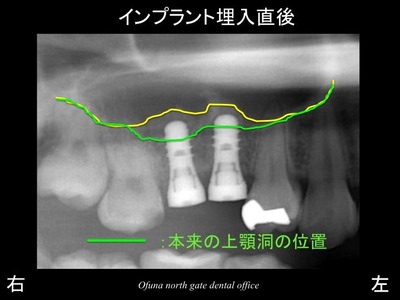

以下は、インプラント埋入直後です。

黄色線がソケットリフト法 によって押し上げられた上顎洞です。

本来の上顎洞の位置と比較してみましょう!

黄色エリアが今回のソケットリフト法 によって押し上げられた部分です。

この黄色部分には人工骨(βーTCP)が入っているのです。